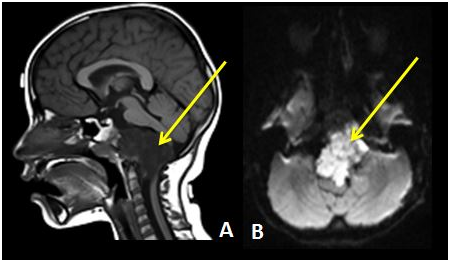

腦干腫瘤以神經(jīng)膠質(zhì)細(xì)胞瘤多見(jiàn),其次是血管網(wǎng)狀細(xì)胞瘤和海綿狀血管瘤。膠質(zhì)瘤中又以星形細(xì)胞瘤和多形性膠質(zhì)母細(xì)胞瘤多發(fā)。膠質(zhì)瘤在腦干內(nèi)多呈浸潤(rùn)性生長(zhǎng),沿神經(jīng)軸向上下兩個(gè)方向發(fā)展,通常腦橋?yàn)楹冒l(fā)部位。星形細(xì)胞瘤多發(fā)生于青少年;室管膜瘤多見(jiàn)于中年人,起源于四腦室底的或頸髓中央管的室管膜。而血管網(wǎng)狀細(xì)胞瘤多發(fā)生于成年人,多由延髓背側(cè)長(zhǎng)出向四腦室發(fā)展,也可完全生長(zhǎng)在延髓內(nèi),還可發(fā)生于延頸髓結(jié)合部或頸髓背側(cè);偶發(fā)于橋腦;其他可發(fā)生在胸髓及眼底等處。而海綿狀血管瘤常中年發(fā)病,多發(fā)于橋腦,其次為中腦、延髓。

腦干腫瘤能活多久?腦干腫瘤的預(yù)后與許多因素有關(guān)。腫瘤的部位、病理性質(zhì)、治療選擇等因素與預(yù)后有關(guān)系。中腦區(qū)腫瘤相對(duì)好于腦橋腫瘤;Ⅰ~Ⅱ級(jí)星形細(xì)胞瘤預(yù)后優(yōu)于多形性膠質(zhì)母細(xì)胞瘤。CT掃描表現(xiàn)為Ⅰ型者預(yù)后較好,Ⅲ型預(yù)后差。腫瘤大小亦與預(yù)后有關(guān),腫瘤越大,預(yù)后越差。根據(jù)腦干腫瘤的手術(shù)經(jīng)驗(yàn)表明: